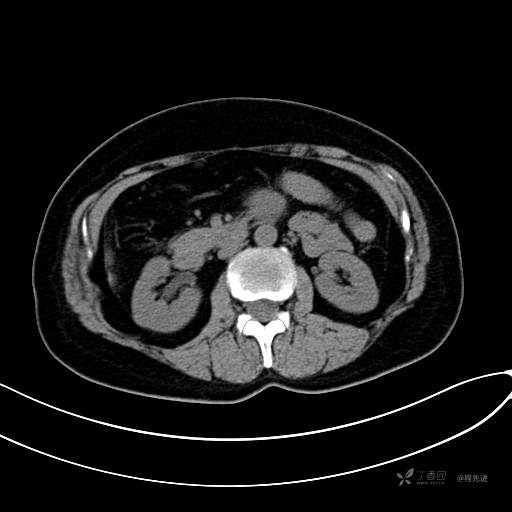

CT增强静脉期